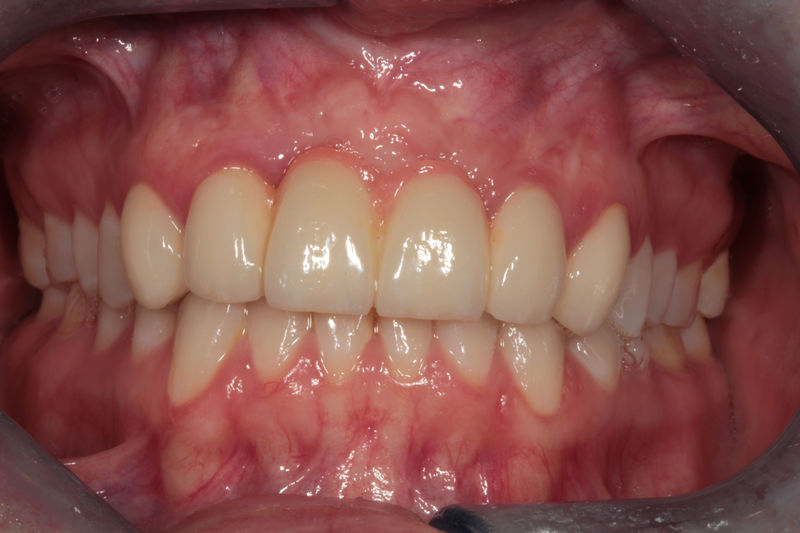

Implante fracasado, extracción, carillas, coronas y prótesis fija.